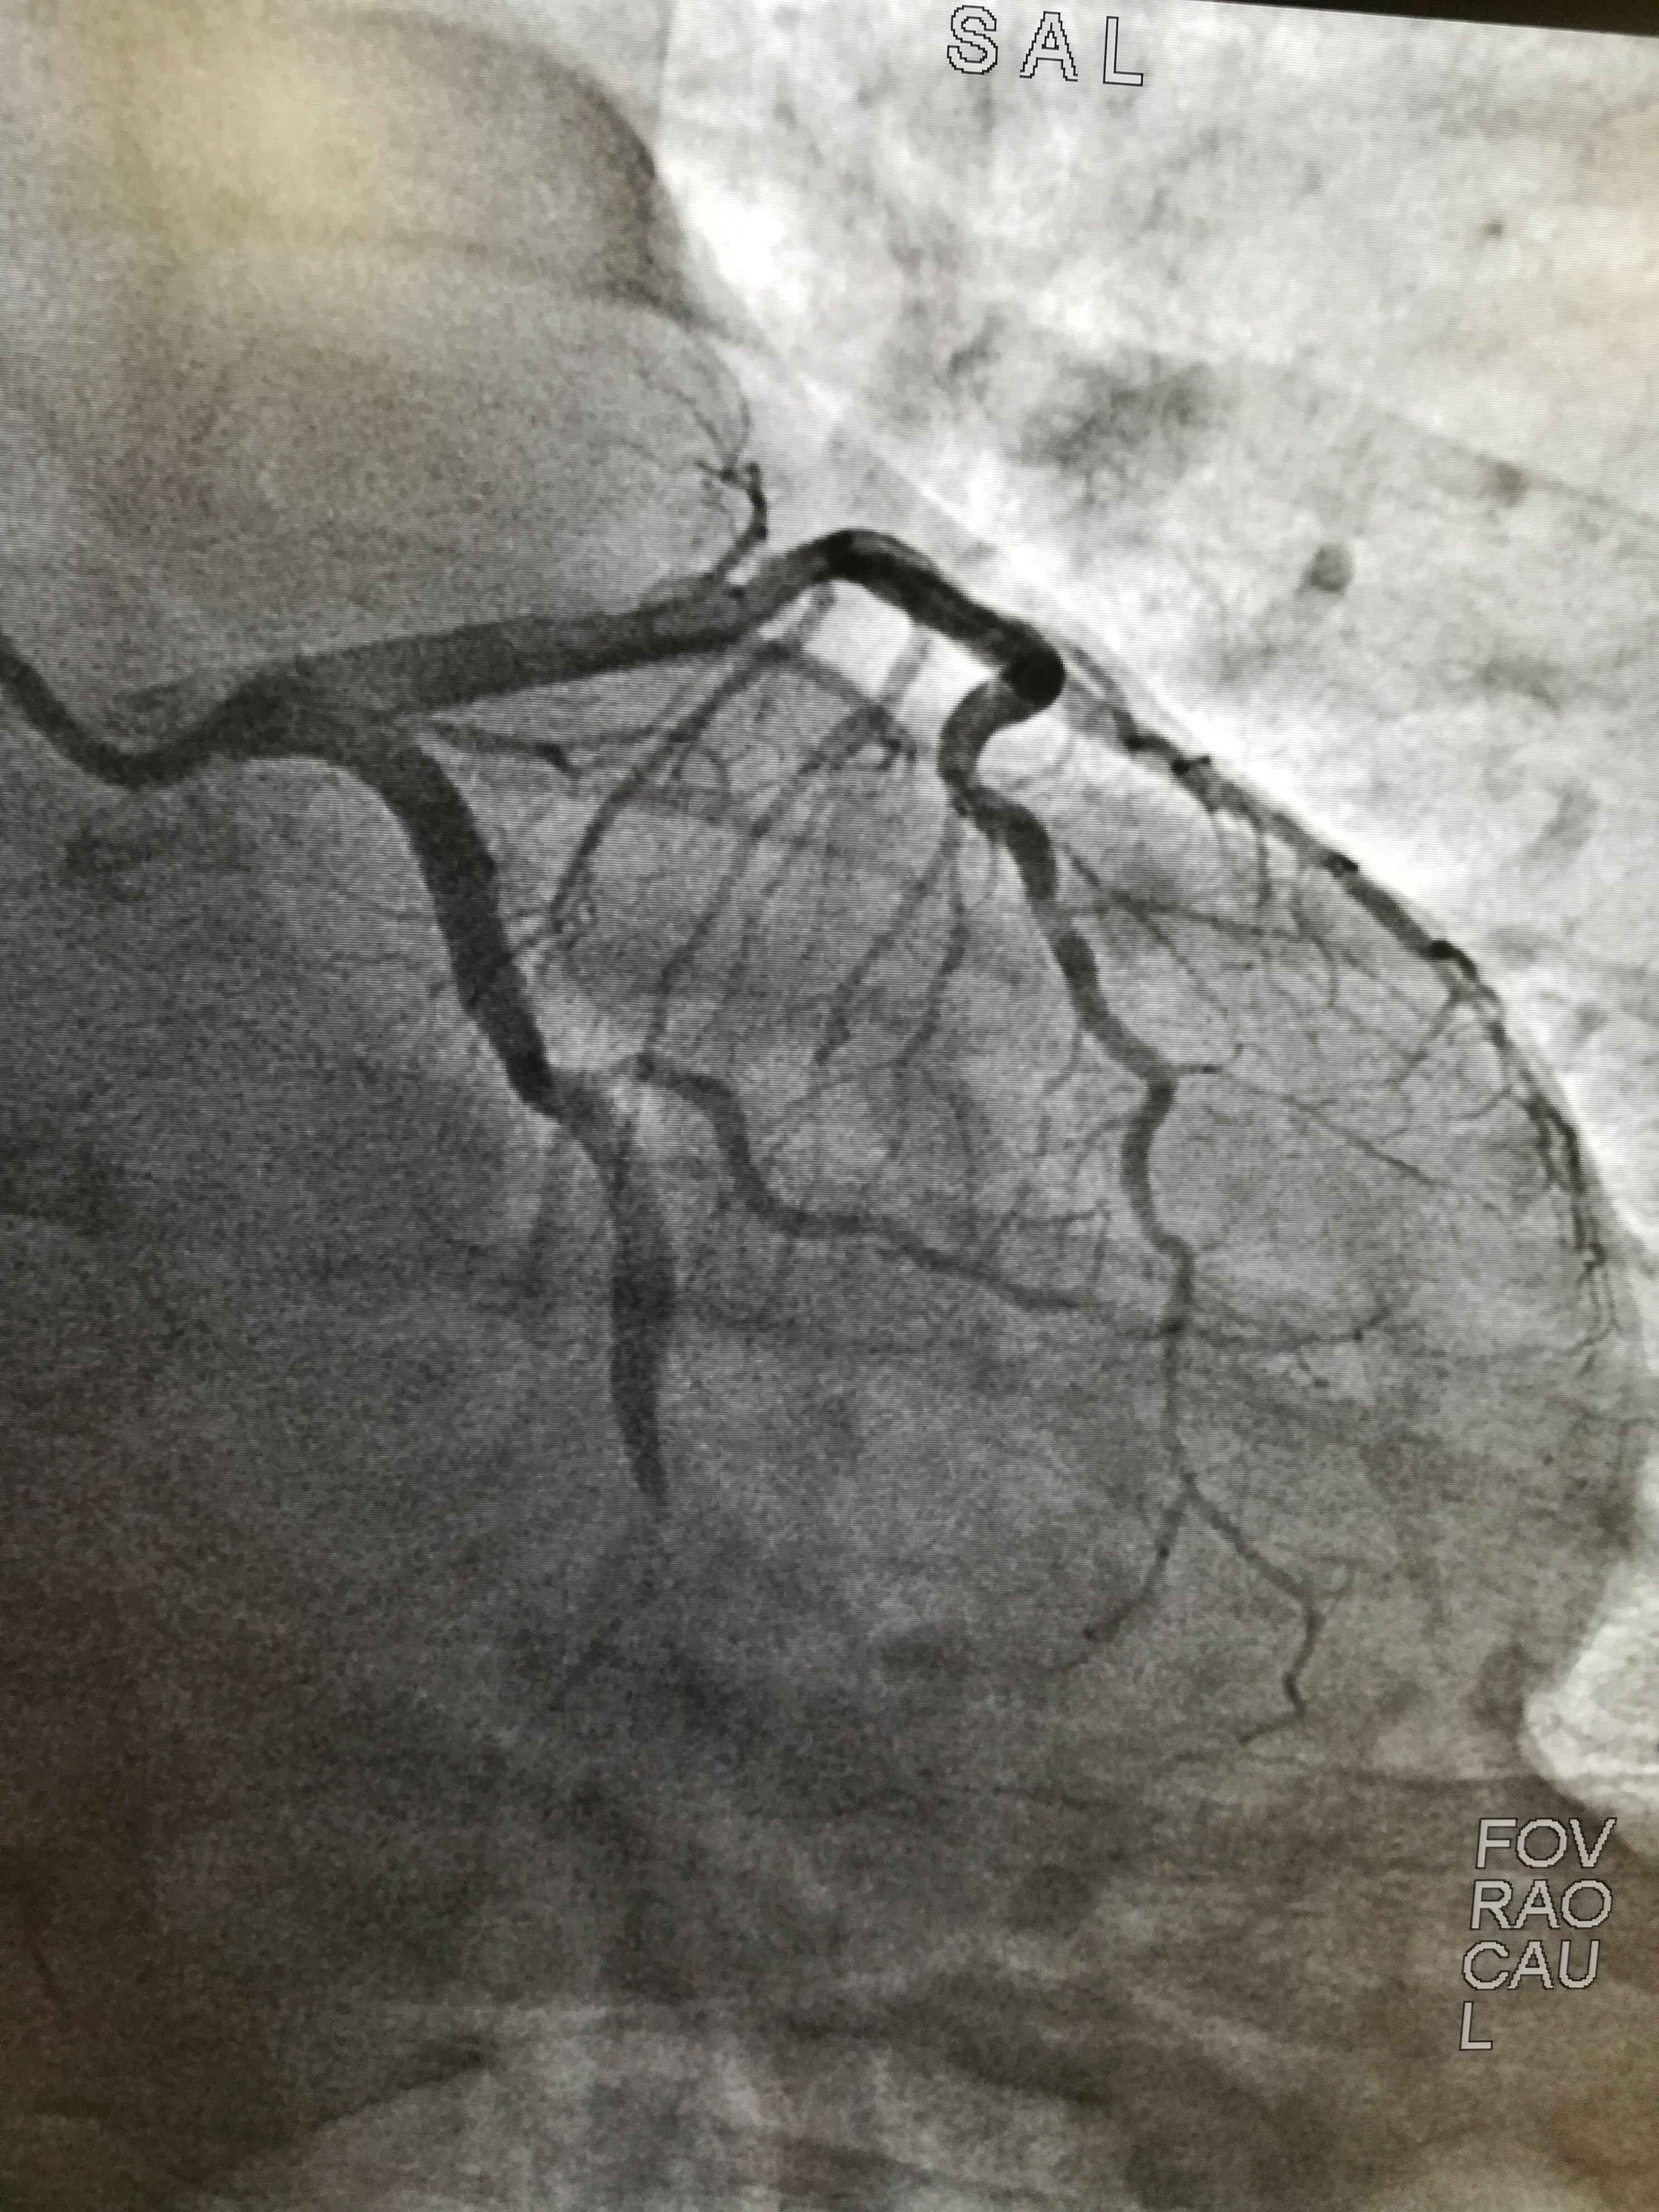

这是经过抢救以后,心脏植入支架以后的血管图形。病人到了有效治疗。